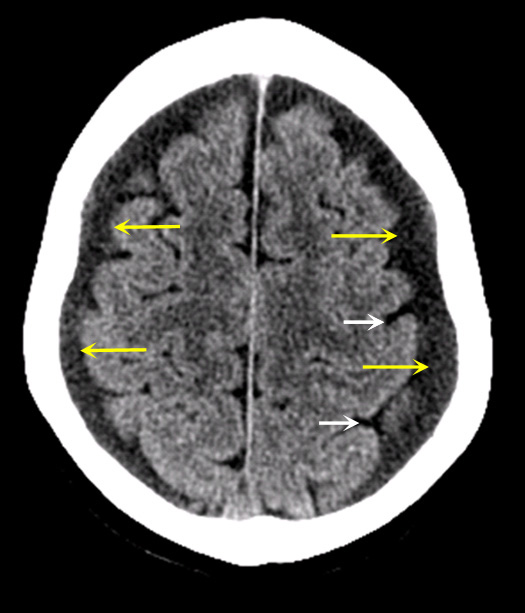

Case 3:

Imaging findings:

Figure 3: Pre-contrast CT

- Bilateral chronic subdural hygromas (yellow arrows) producing slight compression of the adjacent cortical sulci (white arrows).

- As the blood clot further liquefies, the subdural appears hypodense by CT imaging and reaches close to fluid density of cerebrospinal fluid within the cortical sulci/ventricles thus reaching the chronic stage (hygroma).

- Can be asymptomatic or can gradually increase in size leading to brain herniation.